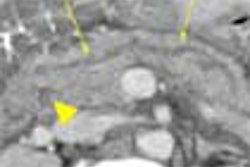

| Results in 20 patients show that calcium mass offers less variability than Agatston or calcium volume measurements as image noise increases. Dose settings on the x-axis were adjusted by the simulation software; individual patient results and BMI were plotted separately for each calcium-scoring method. Chart courtesy of Dr. Joseph Schoepf. |

Commenting on additional charts that showed the accuracy of each scoring method broken down by patient and BMI, Schoepf said that while the Agatston method was accurate over the full range of radiation doses in slim subjects with a low body mass index (BMI 20-25), variation rose significantly in patients with higher body mass, as in the phantom study.

"If you apply the volume score instead of the Agatston score, the overall variability from baseline decreases from 95% to 55%," Schoepf said. "Even with the (larger-sized) group, body mass up to 45, you stay accurate over a broader range of scanner settings. And that's truer for the mass score, again the overall variability is much smaller (35%) as compared to the Agatston score and the volume score. This means that mass indices can be assessed accurately even with very low radiation doses."

The maximum variations at low-dose settings compared to baseline scores at full-dose scanning were 55% for the Agatston method, 30% for calcium volume and 13% for calcium mass. Image noise levels more than doubled with decreasing dose.